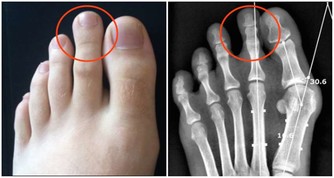

3、痔瘡也是因為缺乏維生素B2引起的。

輕微缺乏維生素B2人體不會有任何感覺,但到一定程度時就會出現明顯的癥狀,首先,在人體最薄弱的地方,通常是消化道的首尾兩端,即口腔或肛門的局部,出現充血、腫脹,隨後皮膚或粘膜出現潰瘍,然後開始出血,這即是口腔潰瘍和痔瘡。如果長期缺乏維生素B2,那麼人體其它部位也會出現同樣的癥狀。

主要原因在於血管,構成血管壁的細胞離不開維生素B2,當缺乏維生素B2時,血管壁(主要是毛細血管,管壁本身就很薄)開始變薄,在血壓的作用下,血管開始向外凸起,當局部的血管都開始鼓起時,就形成了腫塊,最後血管開始裂開出血,如果發生在腦部,你猜到了嗎?對,這就是腦溢血。